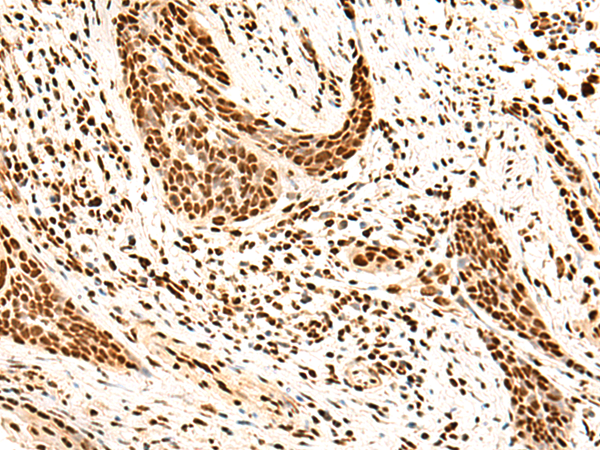

分类: 科研抗体货号: P10059别名: Msl1; U2B''应用: WB,IHC反应种属: Human, Mouse